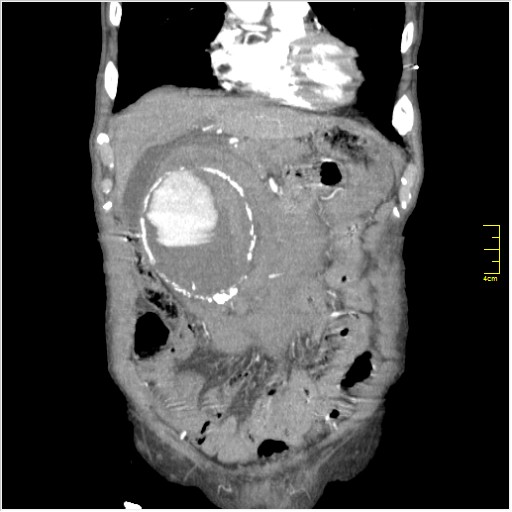

КТ брюшной полости. Мужчина с пальпируемой опухолью в животе

Пациент Т. 64 года, обратился на КТ брюшной полости амбулаторно (!), по направлению семейного врача с диагнозом abdominal mass, буквально: образование брюшной полости.

ТУберкулез позвоночника с обширной деструкцией и с натечником (Вообще-то, я КТ не занимаюсь. Была бы УЗ картинка...)

Huge abdominal aorta aneurism. Simple renal cortical cysts (Bosniak type 1).